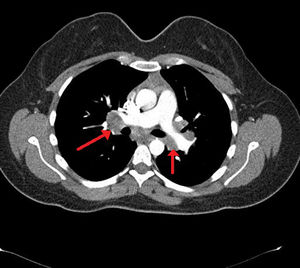

Case presentationA 24-year-old male patient admitted to the Rheumatology polyclinic with complaints of arthritis of both ankle joints, erythema nodosum and fatigue for about 4 years ago. Chest disease consultation was made due to acute phase reactant elevation and detection of bilateral hilar lymphadenopathy at thorax computed tomography (CT) (Fig. 1). Non-caseating granuloma was detected in endobronchial ultrasound (EBUS) biopsy which was made with sarcoidosis pre-diagnosis. Sarcoidosis was diagnosed also due to high CD4/CD8 ratio in the bronchoalveolar lavage (BAL) fluid, typical thorax CT images and biopsy results. The disease was controlled by low-dose corticosteroid therapy and drug was discontinued after about 1 year. Six months after the treatment was discontinued, patient applied to the Rheumatology polyclinic because of complaints of fever, diffuse maculopapular skin rashes, joint pain and morning stiffness. In physical examination; fever 39°C, bilateral axillary lymphadenopathy, mild hepatosplenomegaly, widespread skin rash, tenderness and limitation of motion in knee, wrist, metacarpophalangeal (MCP) and proximal interphalangeal (PIP) joints were detected. Laboratory tests revealed acute phase reactants and ferritin elevation. Serological examinations including rheumatoid factor (RF), anti-nuclear antibody (ANA), anti-cytoplasmic antibody (ANCA), anti-cyclic citrullinated antibody (anti-CCP) were normal. Due to the fever, an infectious disease specialist consultation was made for possible infection, no infection focus was detected. Blood and urine culture results were negative. Viral serologic tests (EBV, CMV, HIV, HBV, HCV) and Brucella tests were normal. Peripheral blood smear was performed, everything was normal except neutrophilic leukocytosis. Hematology consultation was performed, hematological malignancy was not considered. Mild hepatosplenomegaly was detected in abdominal ultrasonography (USG) and axillary USG showed lymphadenopathy with 5–6 lymph nodes and the largest one was 12×4mm in diameter. Chest X-ray and thorax CT were normal. There were no findings suggestive of sarcoidosis activation. According to clinical, laboratory and serological tests the patient was diagnosed with AOSD and corticosteroids (CS)1mg/kg/day plus methotrexate (MTX) 15mg/week were started. After 3 months, there was a slight decrease in acute phase reactants, but there was no significant decline in patient complaints and MTX dose was increased to 20mg/week. After 5months of treatment Tocilizumab was started in a rheumatology center to the patient who applied without any significant regression in his complaints. Significant regression was observed in the patient's complaints at 6th month of this treatment, acute phase reactants and serum ferritin levels were normalized. Policlinic follow-up of the patient with good general condition and remission of the disease is continuing.